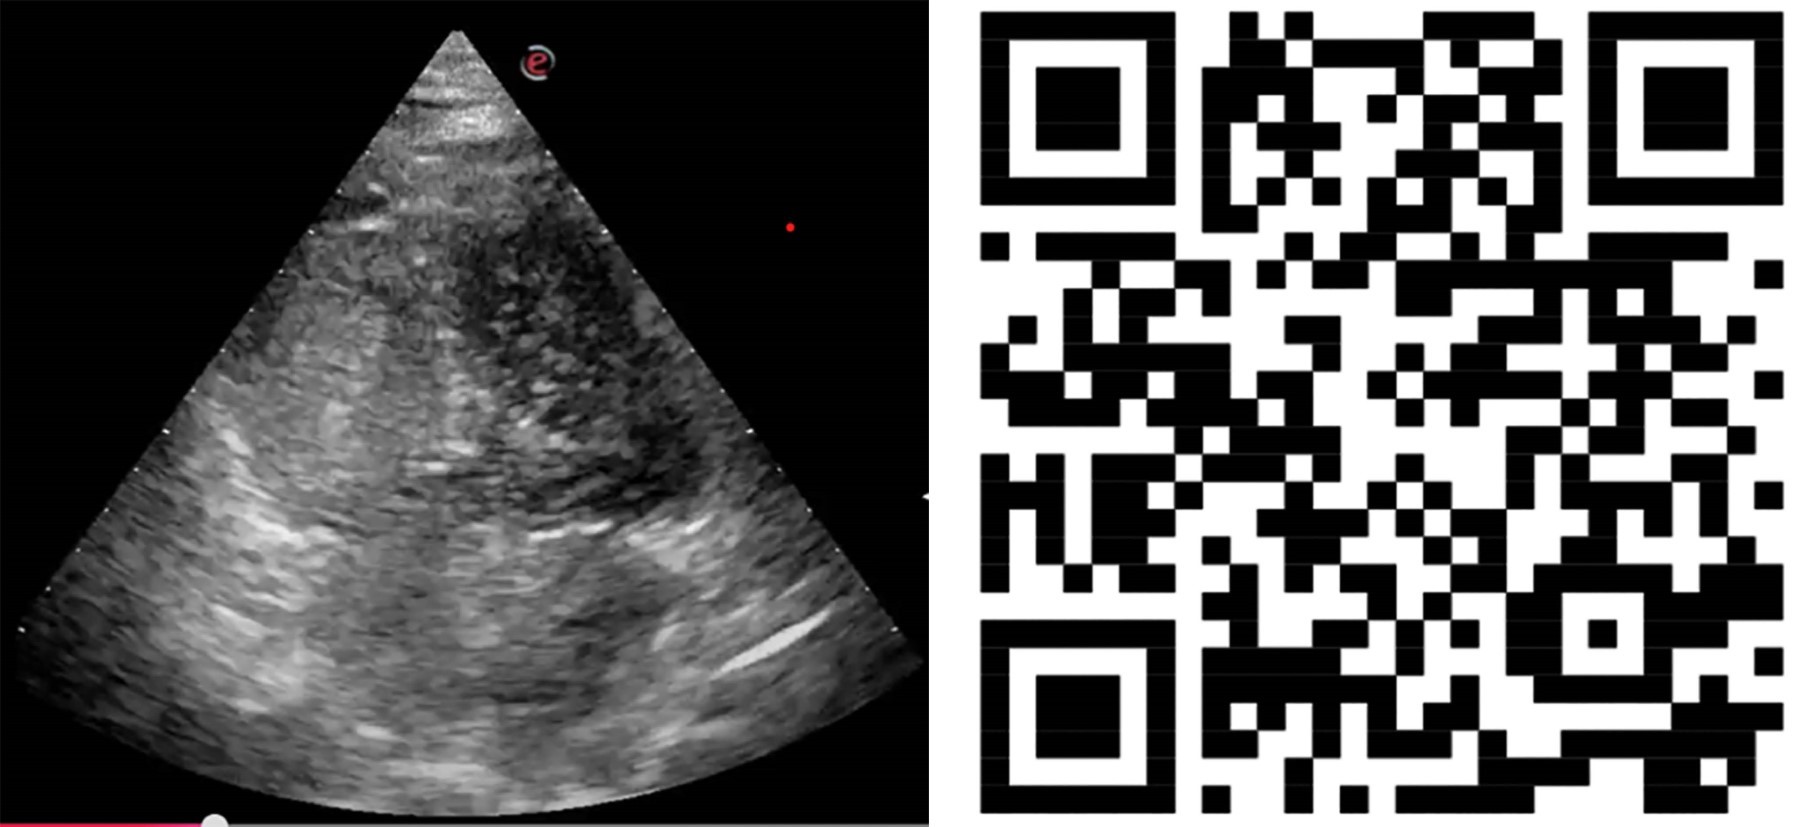

Figure 2